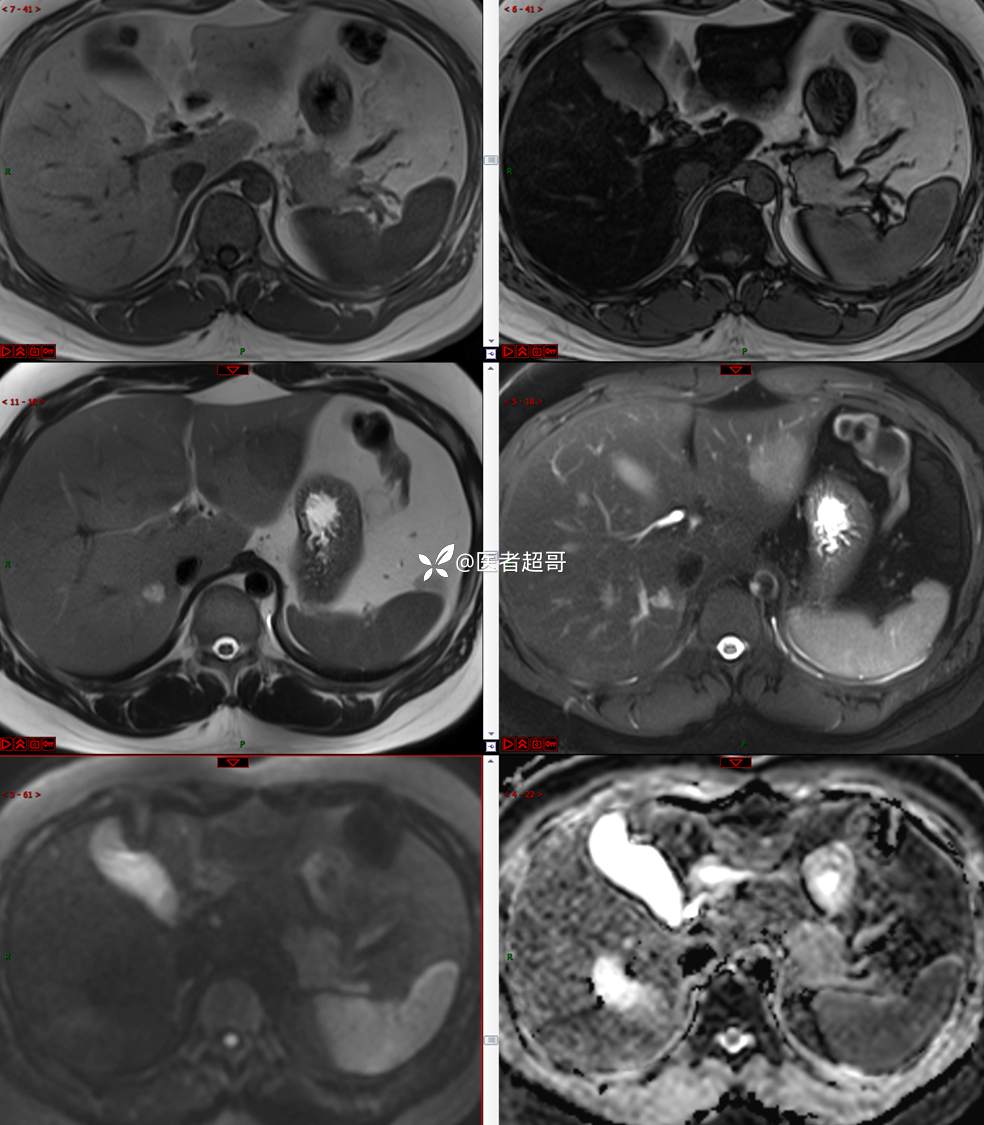

【影诊笔记800】青年男性,肝脏占位,特殊对比剂提示富血供,您能想到啥?有结果!

男,31y

主 诉:发现肝占位性病变5天。

现病史:患者缘于5天前体检时发现肝占位性病变,未予以特殊处置。现患者为求系统诊治就诊于我院,行普美显提示:肝左叶富血供占位,请结合临床及其他检查,肝多发血管瘤,脂肪肝,肝囊肿,请结合临床。门诊以“肝占位性病变”收入我科。病程中,饮食睡眠可,二便可,近期体重未见明显变化。